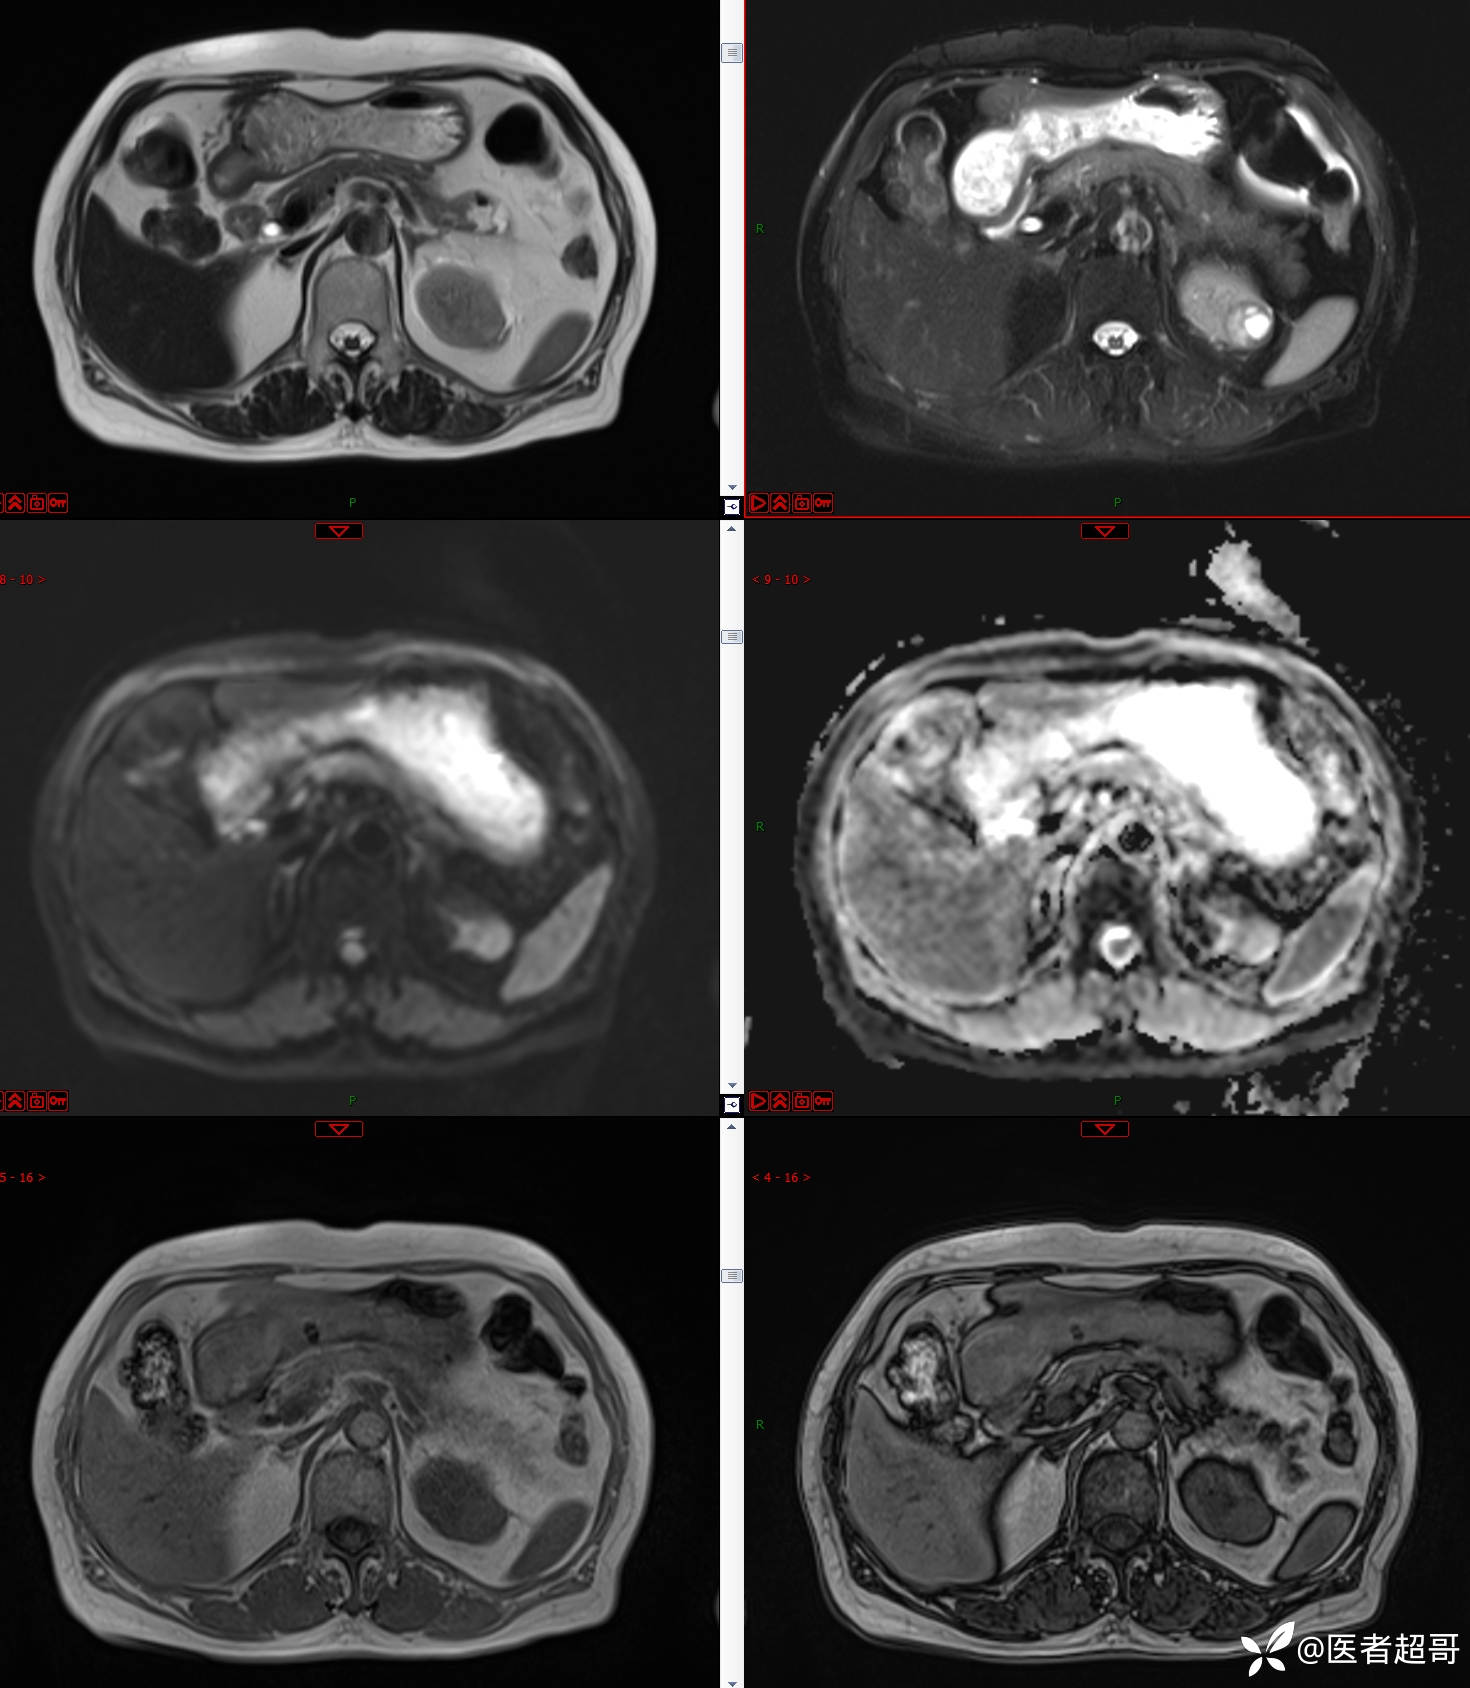

左肾占位2个月就诊,有病理,请分析!

主 诉:查体发现左肾占位2月。

现病史:患者自述2月前于镇中心卫生院行腹部超声发现:左肾实性占位。患者无尿频尿急尿痛,无发热寒战,无恶心呕吐。未行特殊治疗。现患者为求进一步诊治,就诊我院,门诊以“肾肿物”为诊断收入院,患者自发病以来,神志清,精神可,饮食可,睡眠一般,大便正常,体重未见明显改变。